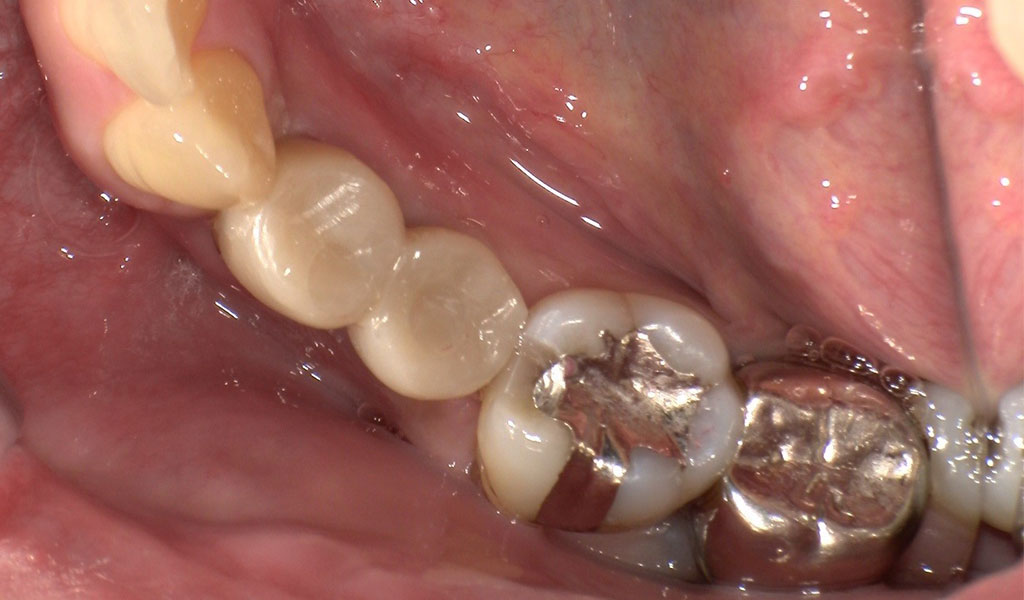

Before1

After1